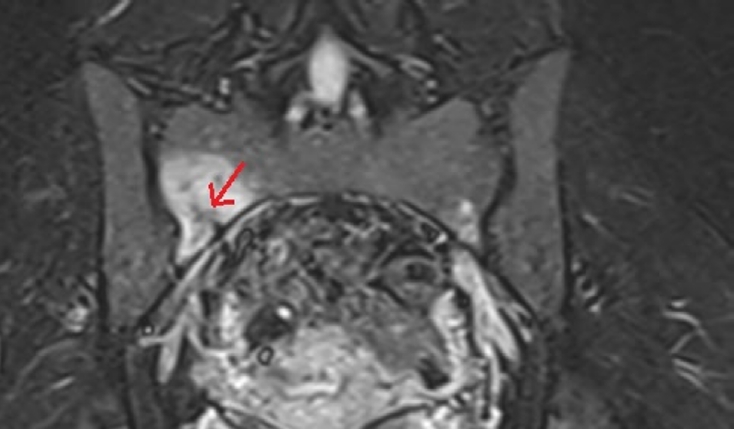

Sacral stress fracture mimicking sacroiliac pathology in two young adults: a reminder to systematically review the sacrum on hip/sacroiliac magnetic resonance imaging

Nihal Karayer Özgül, Sami Özgül

J Musculoskelet Trauma 2026;39(2):181-183.   Published online February 25, 2026

DOI: https://doi.org/10.12671/jmt.2026.00038